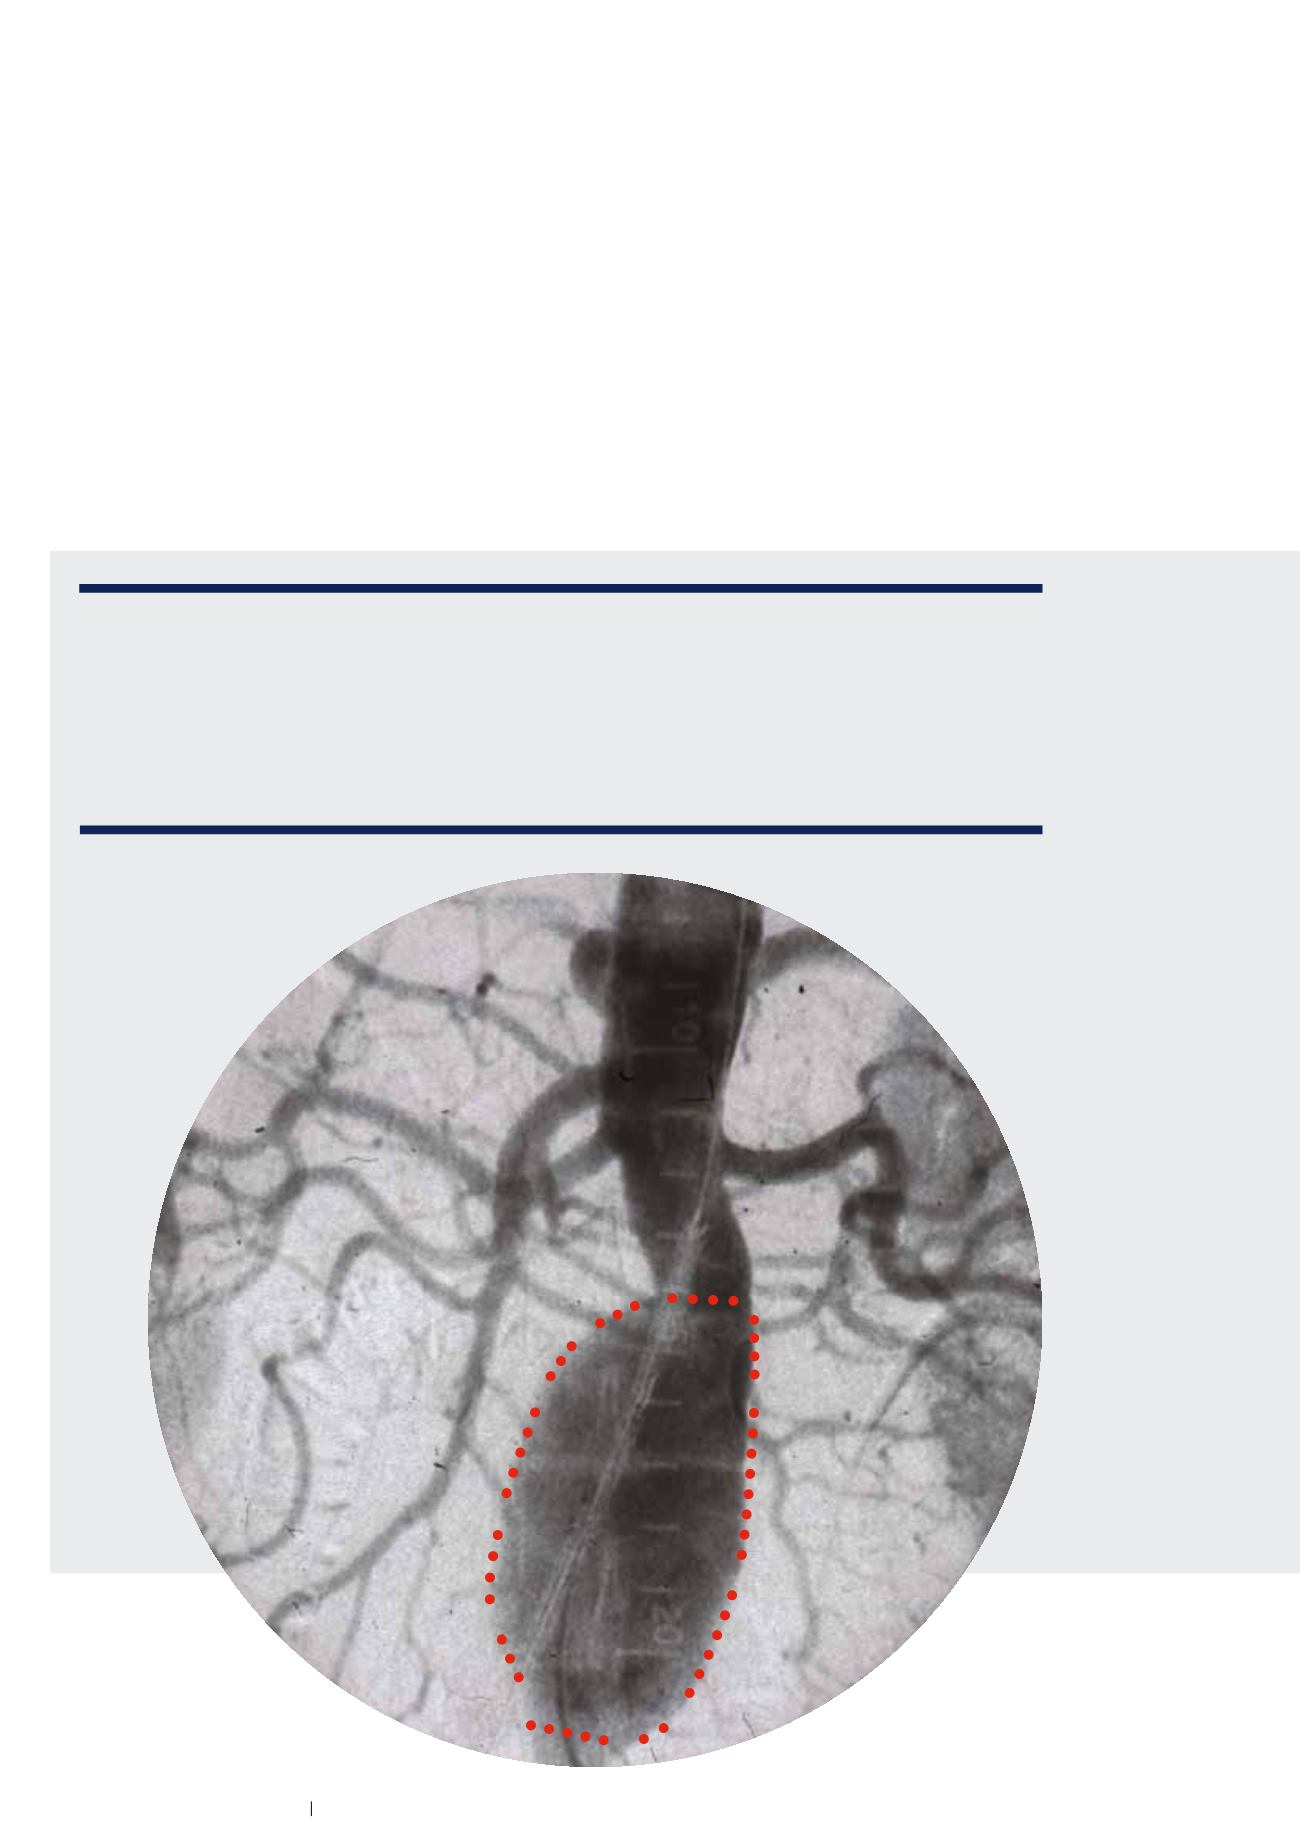

Aufnahme eines Bauch

aortenaneurysmas vor

der Operation